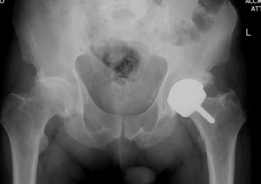

A standard radiographic series of the right hip was obtained, including an anteroposterior pelvis, a cross-table lateral, and a Dunn lateral view.

Image

The anteroposterior pelvis radiograph demonstrated severe, end-stage osteoarthritis of the right hip. Findings included complete obliteration of the superolateral joint space, extensive subchondral sclerosis, and large osteophyte formation at both the acetabular rim and the femoral head-neck junction. Subchondral cystic changes were evident in both the acetabular dome and the weight-bearing portion of the femoral head. The Tönnis grade was classified as Grade 3.